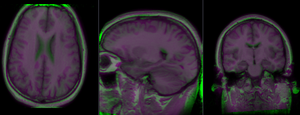

Registration Results

RegLib C10 unregistered.png unregistered (click to enlarge)

RegLib C10 registered1 Affine.png after affine registration (click to enlarge)